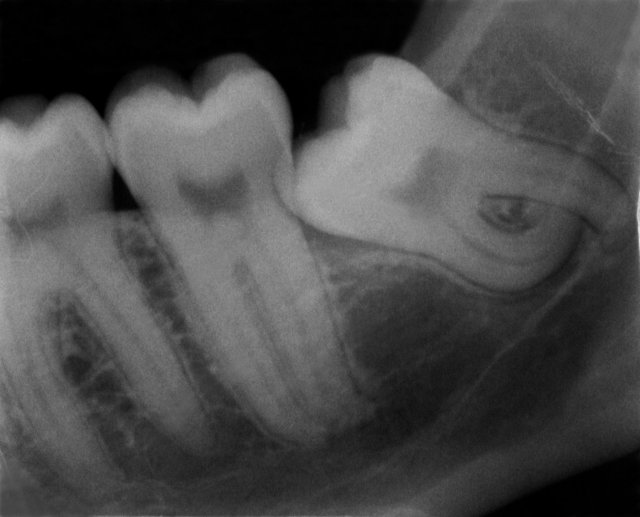

Verlagerung und Retention

Tiefe Karies wegen eines benachbarten Weisheitszahnes

Tiefe Karies wegen eines benachbarten Weisheitszahnes ...